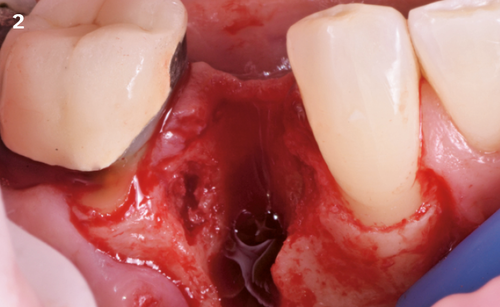

"After the extraction, I realized that the buccal wall was missing and I had to leave the membrane exposed. The regenerative potential of the site could be poor, so I decided to boost the biomaterials’ effect with polynucleotides and hyaluronic acid."

The Situation

The patient (45 years old, female, non-smoker, no previous pathologies) is referred for extraction of tooth 45 and immediate implant placement. The site showed an increased probing depth and a marked bone loss.